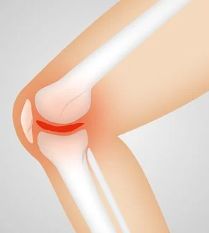

무릎통증 원인 2. 연골 손상

무릎 관절연골의 손상도 무릎통증의 원인 중 하나입니다. 이는 연령이든 스포츠를 하든, 무릎을 부상해 발생할 수 있습니다. 연골 손상은 무릎관절의 안정성을 해치며, 무릎에 국한된 통증뿐만 아니라, 다리 전체에 통증을 느끼게 합니다.